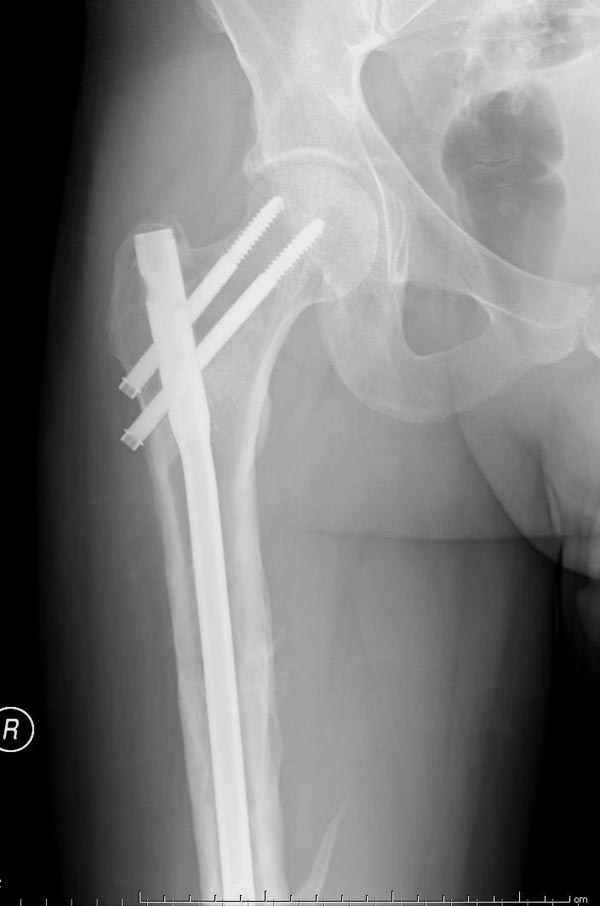

Мы не дождались “Happy End”, у больного IQ в пределах 70%, через 6 месяцев вернулся после небольшой травмы, споткнувшись получил перелом

того же бедра (рис №7).

На следующий день произвели интрамедуллярный остеосинтез: этапы во время операции (рис №8, №9)

и последующих снимках (рис №10, 11, 12, 13) перелом сростается и передвигается с полной нагрузкой.

При обзоре причин перелома, на снимке №2 обнаружили, что один из стержней аппарата наружной фиксации проходил только через передний кортекальный слой, что создало стрессовую зону на бедре и в результате перелом из-за незначительной травмы.